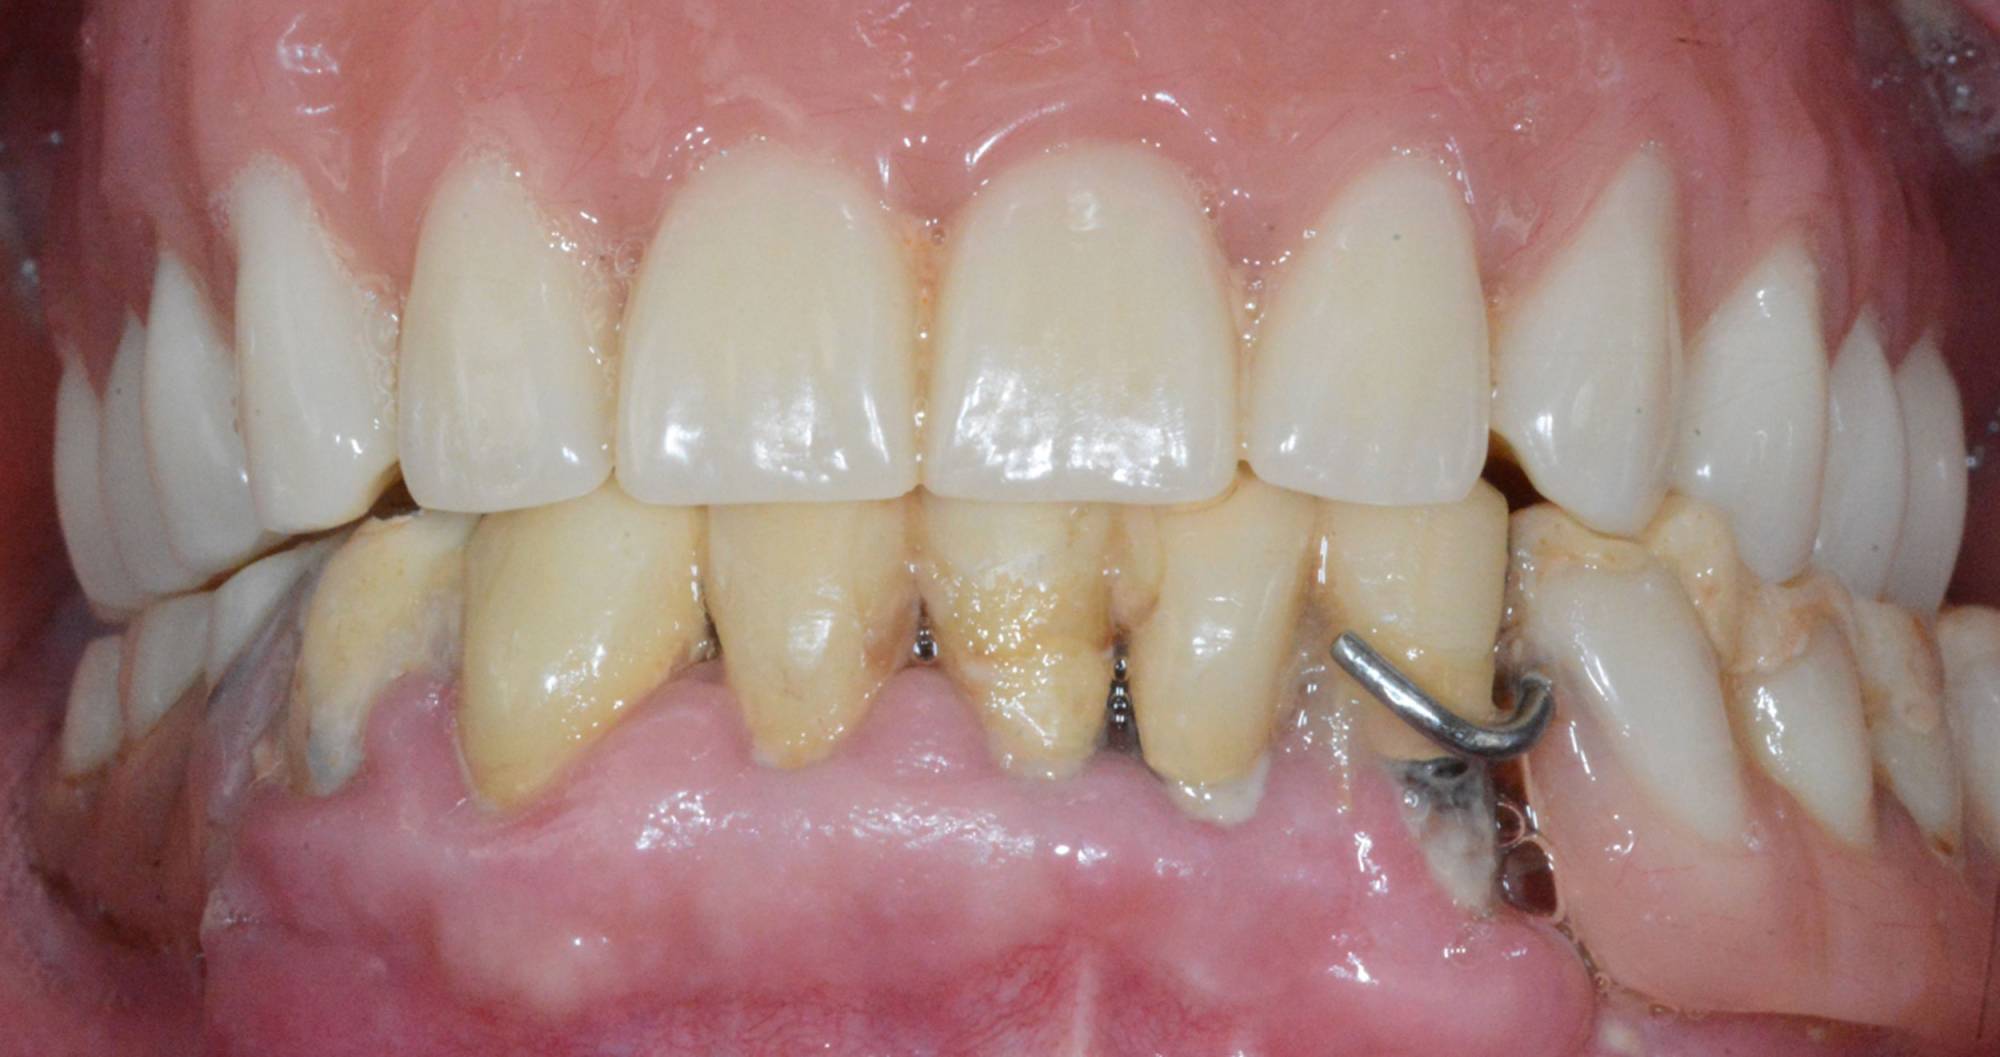

L'impianto dentale osteointegrato è una sorta di radice artificiale che si inserisce nell’osso del paziente, per rimpiazzare un dente mancante.

Quasi tutti possono ricorrere agli impianti, poiché sono una soluzione che presenta solo poche controindicazioni di carattere generale. Anche nei casi in cui non vi sia una sufficiente quantità d’osso per inserire l’impianto, è possibile ricorrere a tecniche di rigenerazione ossea guidata utilizzando biomateriali specifici e porzioni d'osso prelevate dal paziente stesso, per ricostruire la parte ossea mancante.